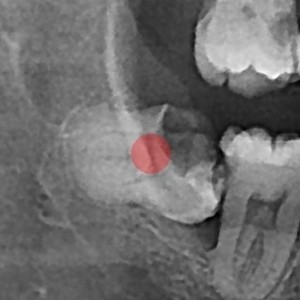

사랑니발치 충치가 심한 사랑니

98c9148a81c37bd910ebd0e3dd27d654_1764730644_2549.jpg